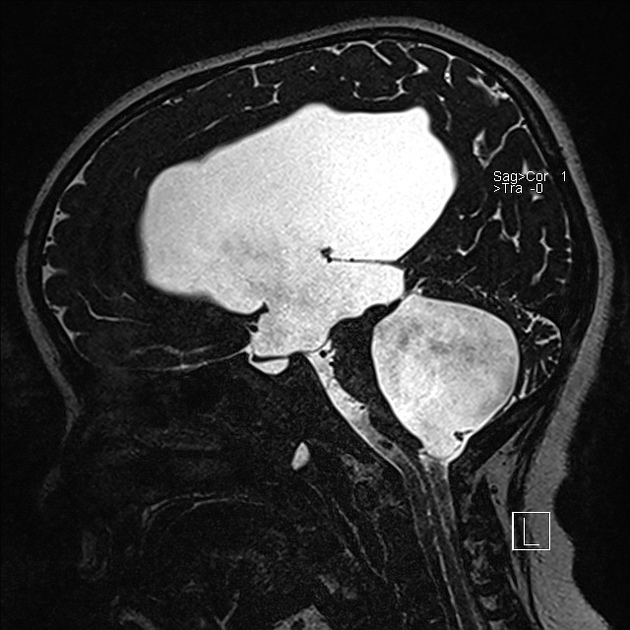

Marked obstructive hydrocephalus due to fourth ventricular outlet obstruction by fine septations

dandy walker malformation

This case illustrates a classic Dandy Walker malformation with associated aqueduct stenosis and obstructive hydrocephalus, a common associated feature

(although not part of the Dandy walker triad: